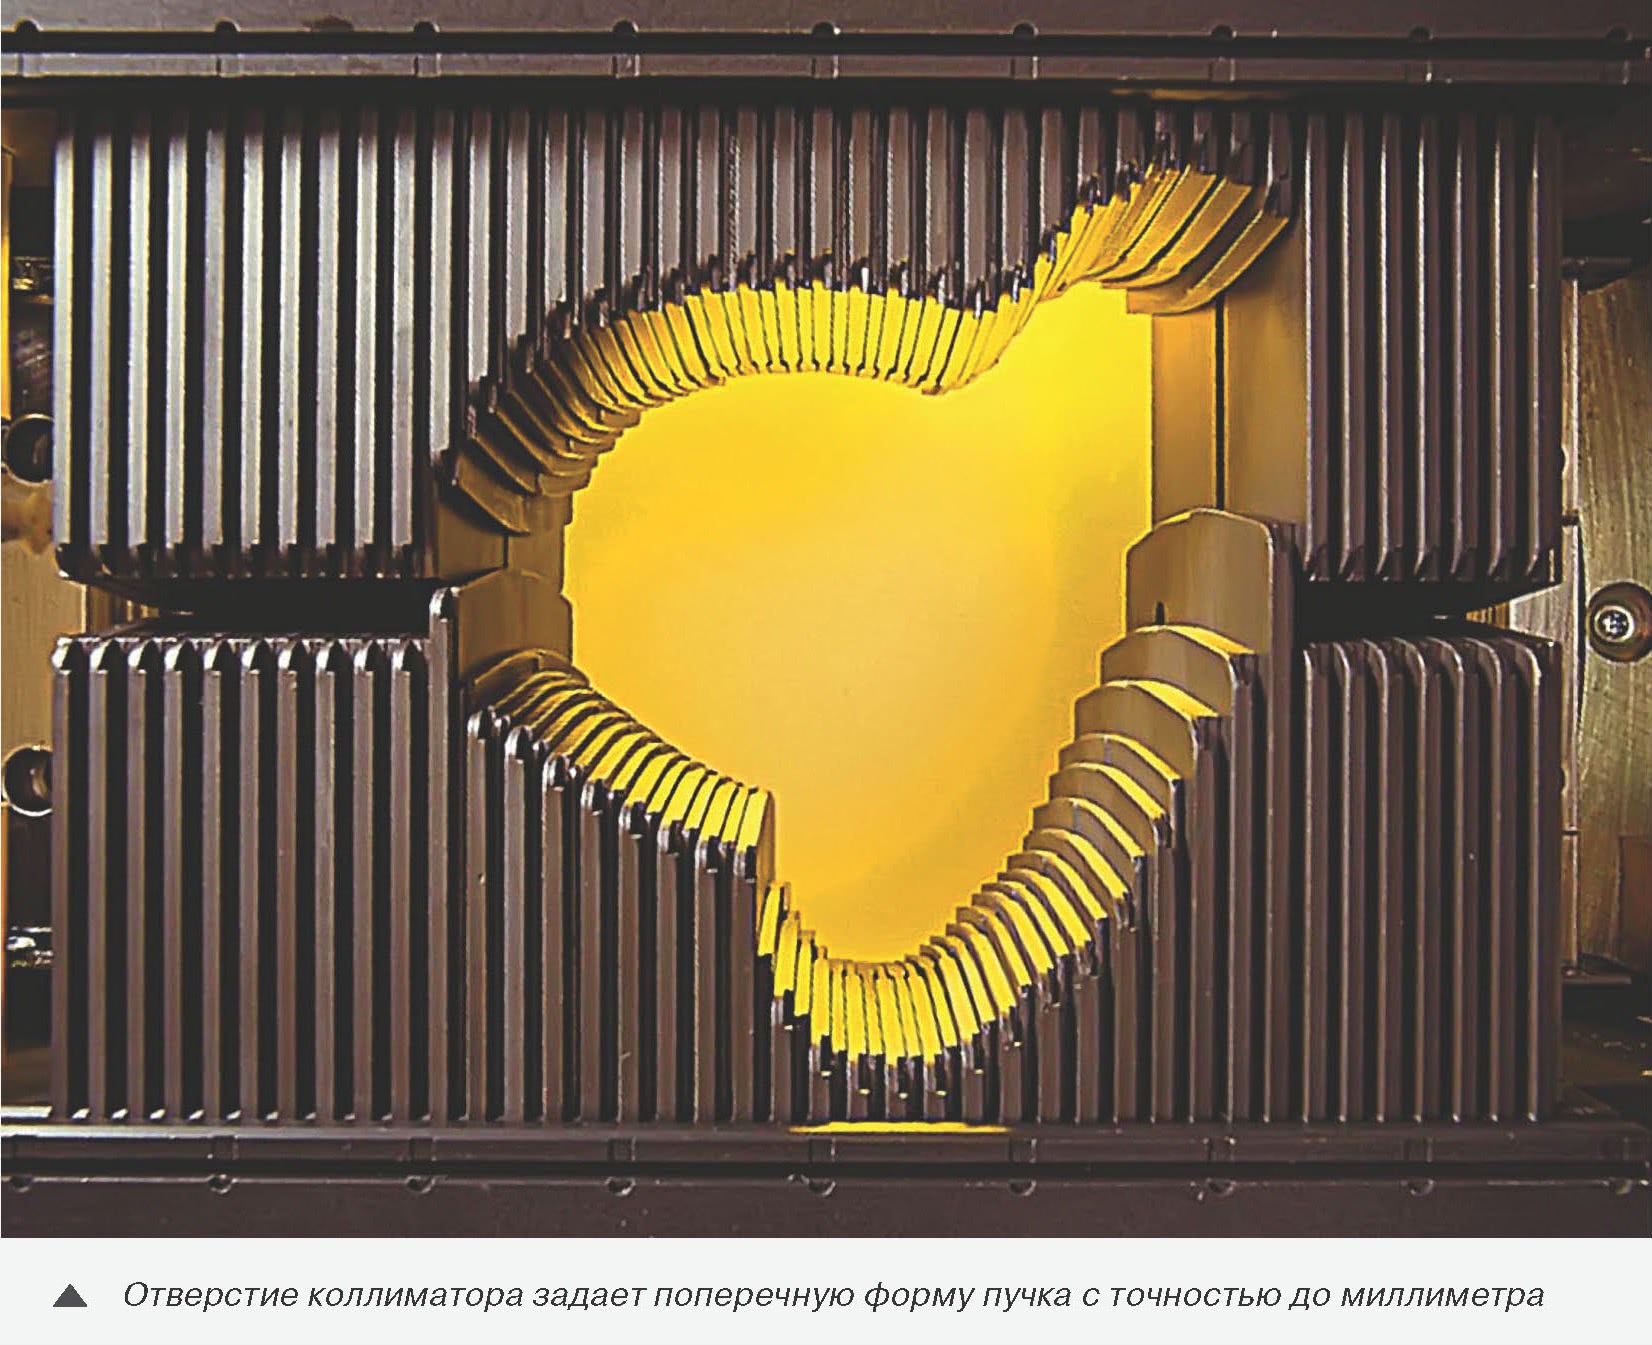

Второй шаг: информацию о форме и размерах опухоли в цифровом виде вводят в трехмерную компьютерную систему планирования облучения. Врач-радиолог обозначает на каждом томографическом срезе контур мишени и структуры организма, которые не должны быть повреждены (например, нервы). По намеченным врачом контурам компьютерная программа создает трехмерные модели структур. После этого врач-радиолог выбирает дозы и направления облучения (направлений может быть от двух до семи). Программа beams-eye-view («взгляд на мишень со стороны пучка») определяет форму поперечного сечения протонного пучка, которую должен воспроизвести коллиматор.

Третий шаг: изготовление фигурных коллиматоров и компенсирующих болюсов. По заданной форме поперечного сечения пучка подбирается материал цилиндра коллиматора (чтобы если нужно – ослабить пучок, поглотив в стенках цилиндра часть протонов) и рассчитывается форма его отверстия. Исходя из распределения назначенной пациенту дозы и границ протонного пучка по глубине мишени, рассчитываются и затем изготавливаются болюсы. Их форма должна учитывать неоднородность структуры тканей и органов пациента, расположенных на пути летящих частиц.